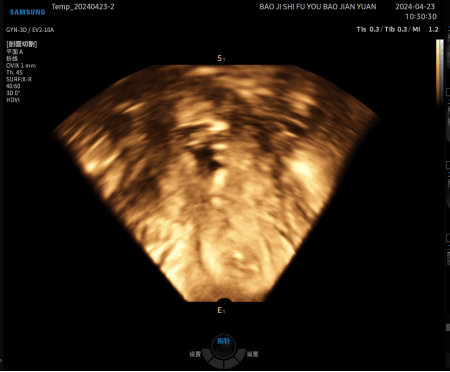

病例再现 / 04

患者外院取环二维超声、x线透视均未发现节育环位置及形态,宫腔水造影清晰可见变形的节育环。